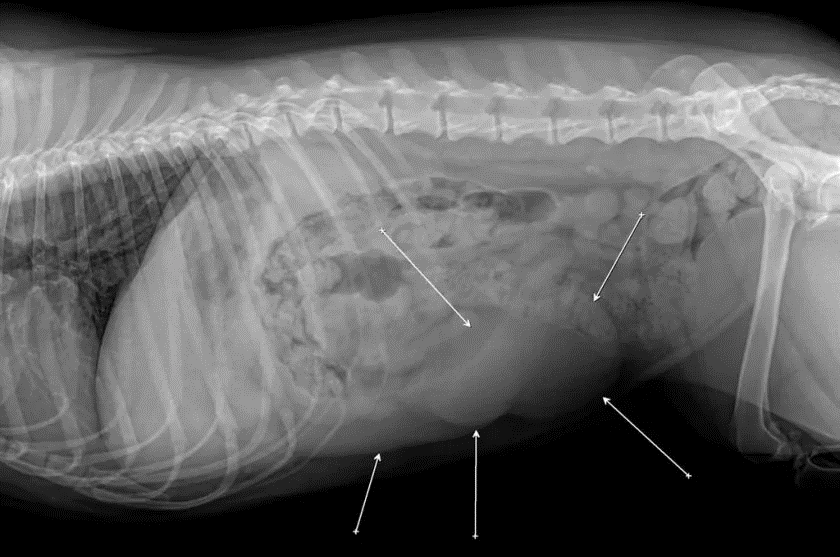

Наиболее распространенным признаком опухоли молочной железы у собак и кошек является хорошо ощутимое образование под кожей живота. Однако есть и другие признаки, и симптомы: характерные выделения из молочной железы, болезненные, опухшие груди, язвы кожи над грудью, потеря аппетита и веса, общая слабость и апатия. При появлении таких признаков нужно немедленно обратиться к ветеринару.  Диагностика в первую очередь будет включать тщательный общий медицинский осмотр, который позволит специалисту определить местоположение, размер и общий характер всех новообразований молочной железы и оценить их опасность. Понадобятся и другие процедуры, такие как общий анализ крови, химический анализ, анализ мочи, профиль свертываемости крови, УЗИ брюшной полости, рентгенография и компьютерная томография, которая используется для диагностики рака.  Лимфатические узлы также должны быть исследованы на предмет распространения раковых клеток. Все это позволяет определить характер заболевания и разработать оптимальный метод лечения.